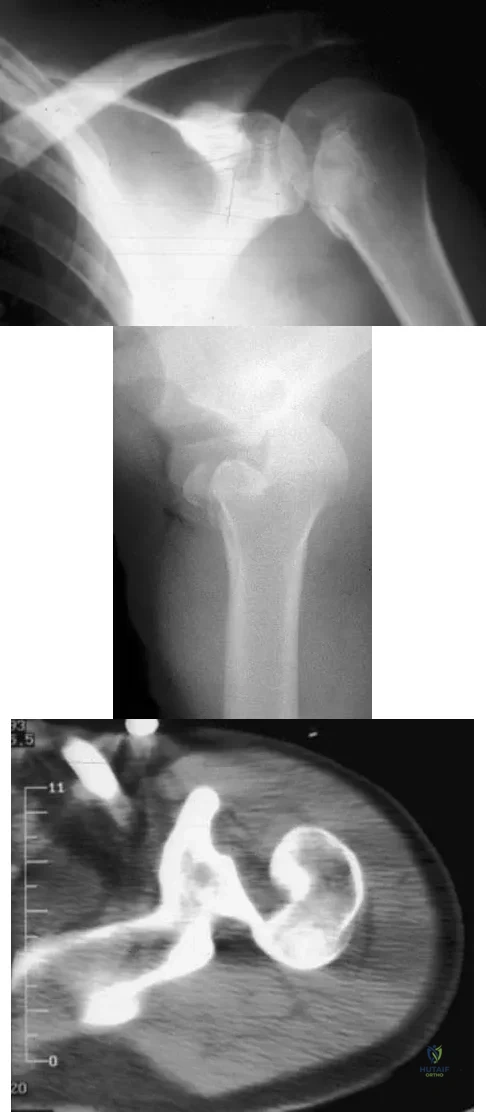

A 21-year-old patient has had pain and a marked decrease in active and passive shoulder motion after having had a seizure 2 months ago as the result of alcohol abuse. Current AP and axillary radiographs and a CT scan are shown in Figures 26a through 26c. Management should consist of

Detailed Explanation